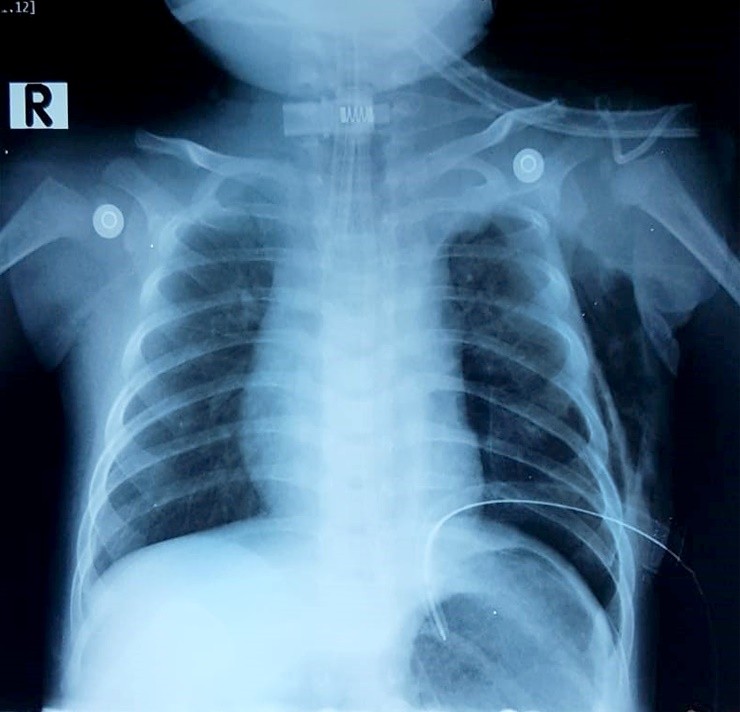

Ngay khi tiếp nhận bệnh nhân, bác sĩ chỉ định chụp X quang, xét nghiệm. Kết quả cho thấy bé bị tràn dịch màng phổi bên trái, gây chèn ép nhu mô phổi. Bệnh nhi bị rò dịch dưỡng trấp nghi do rò từ ống ngực vào khoang màng phổi.

Hình ành chụp X quang cho thấy bệnh nhi bị rò dịch dưỡng trấp nghi do rò từ ống ngực vào khoang màng phổi. Ảnh: BVCC